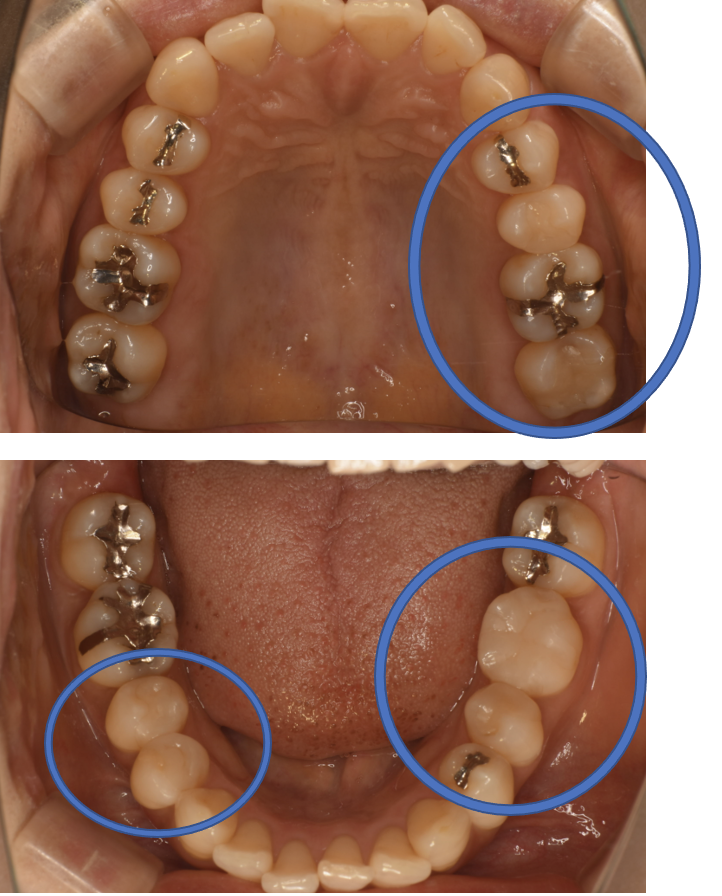

After

| 治療方法 | セラミックインレー(E-MAX In) 虫歯などで失った歯質を天然歯と同じ色・質感のセラミックで補う治療法です。金属を使用する治療と比べて、審美性だけではなく、耐久性や体の負担が少ないという面でも優れていると注目されています。従来のセラミックと比べて天然歯と同程度の強度であり、耐久性が高くなっています。どのくらいもつかは使用状況や部位、メンテナンスの有無などによって大きく変わってきます。透明感があり、キレイで自然な色調を表現できます。歯と分子レベルの化学結合によって吸着するため隙間ができることが少なく、虫歯にもなりにくいと言われています。 そして、金属アレルギーのリスクがありません。 |

| 費用 | ¥69,000×6=¥414,000 |

| 備考 | 院長より 銀歯の内部に虫歯が進行してしまっていたケースです。中を開けて見てみると、外から想像するよりもはるかに虫歯が広がってしまっていました。幸運にも神経を保存できたので、生きた臓器としてまだ使うことが可能です。今回は部分的な詰め物で対応することができたケースです。 |